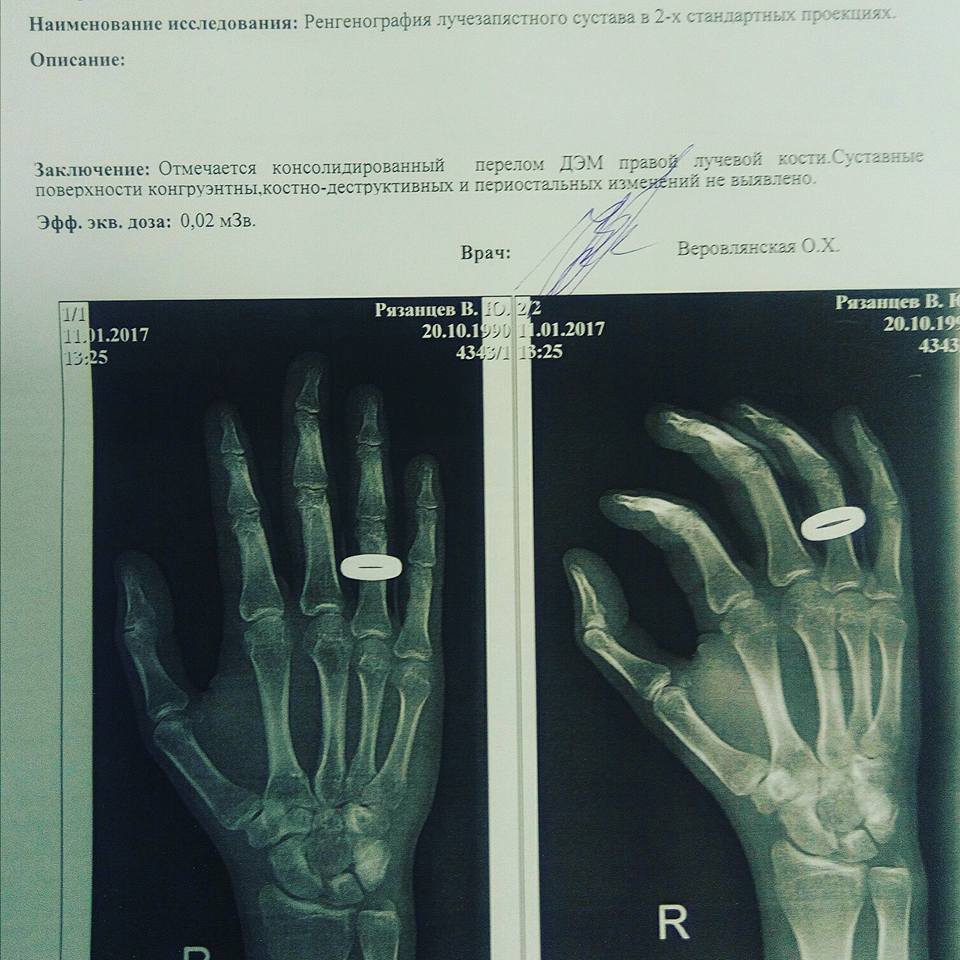

Врачи диагностировали у корреспондента "Кавказского узла" Владислава Рязанцева, избитого накануне в Ростове-на-Дону, перелом кисти правой руки, а также подтвердили закрытую черепно-мозговую травму. К нападению на Рязанцева причастны “русские национал-социалисты”, заявил националист Роман Железнов.

“В поликлинике рентген показал, что у меня есть перелом кисти правой руки. Четыре года назад у меня в этом же месте была травма. Врачи говорят, что, возможно, после избиения старый перелом дал о себе знать. Рука сейчас не сгибается, не разгибается, а общее самочувствие является неудовлетворительным”, - добавил Рязанцев.

В заключении врачей говорится о том, что у Рязанцева диагностирован перелом. Заключение сделано на основе рентгеновского снимка. “Отмечается консолидированный перелом ДЭМ правой лучевой кости”, - говорится в заключении, копия которого имеется в распоряжении “Кавказского узла”.